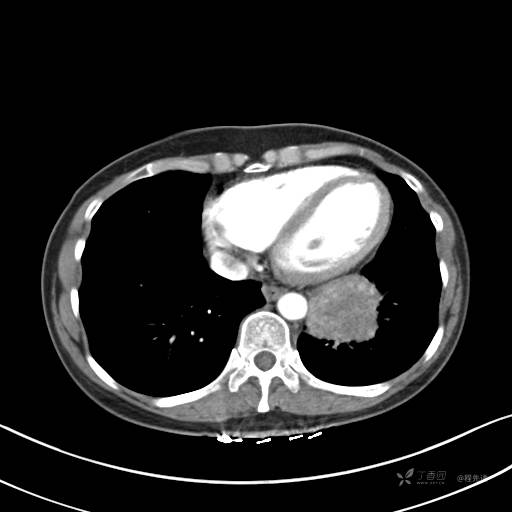

冠状位重建

CT值:平扫:31HU,动脉期:74HU,静脉期:84HU